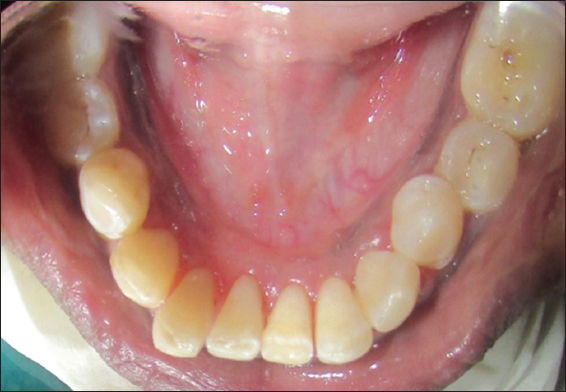

A 22-year-old female patient was reported to the outpatient department with a chief complaint of a growth in the lower front teeth region since 5–6 months earlier with no relevant medical history. The lesion was gradually increased in size from the interdental papilla of lower left lateral incisor with a history of difficulty in mastication and speech. Intraoral clinical examination revealed a pedunculated firm in consistency and well-defined growth in relation to 31, 32, and 33 on the lingual side measuring approximately 1 cm × 1 cm in diameter, extending from distal surface of 31 to mesial surface of 33, upper border covers the middle third level of 31, 32, and 33 pink in color, roughly oval, with overlying smooth surface, and surrounding mucosa is normal and borders are well defined [Figure 1]. On palpation, the growth is non-tender, firm in consistency, mobile, and having pedunculated base. Labial vestibule was apparently normal with respect to 31, 32, and 33 hard tissue examination revealed normal.

Figure 1: Pre-operative